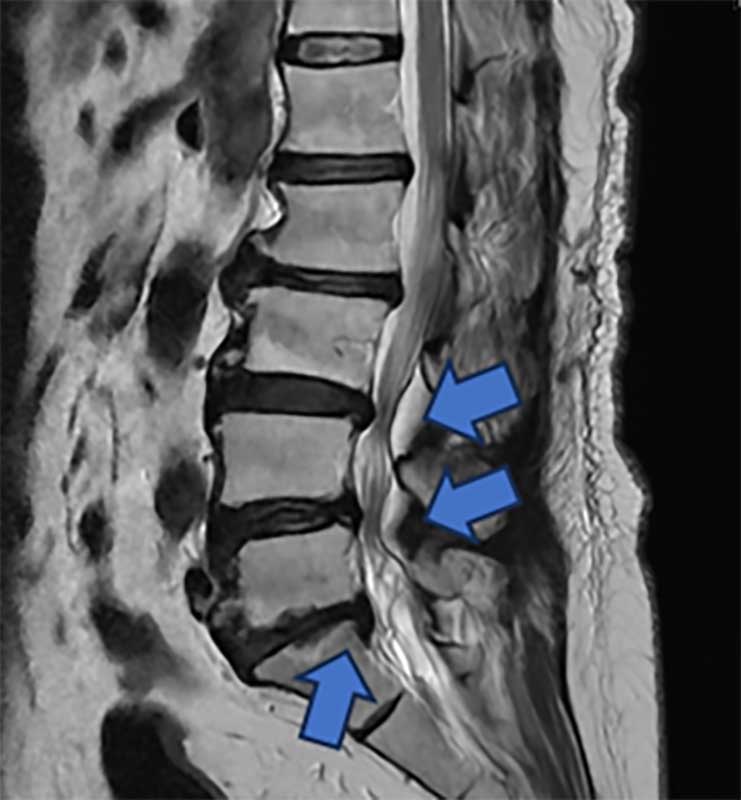

一名65歲婦人,長期飽受腰痛、下肢痠麻及坐骨神經痛困擾,行走距離逐年縮短,嚴重影響日常生活。過去曾接受膝關節保膝手術及脊椎內視鏡減壓治療,初期恢復良好,但因仍存在多節段腰椎退化性狹窄與骨刺問題,加上彎腰負重與久坐習慣未能完全改善,症狀逐漸惡化,甚至出現神經性跛行。經臺中市立老人復健綜合醫院骨科部副部長林琮凱醫師詳細檢查後,診斷為第三、四、五腰椎合併第一薦椎多節段脊椎狹窄與神經壓迫。醫療團隊與病患及家屬充分溝通後,決定採用電腦導航輔助之前位/前側位脊椎融合手術,合併後方骨釘固定,一次完成多節段重建。術後病患神經症狀明顯改善,恢復行走能力,生活品質大幅提升。